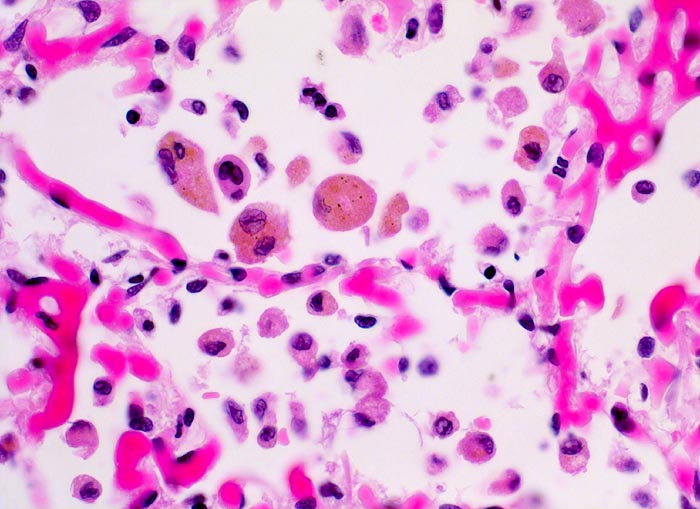

chronische Lungenstauung: Herzfehlerzellen

Die Kapillaren in den Alveolarsepten sind prall mit Blut gefüllt (Stauung). Bei sehr starker Stauung kann ein Teil des Blutes in die Alveolarräume übertreten und wird dort von den Alveolarmakrophagen phagozytiert. Deren Zytoplasma ist mit braungelbem Hämosiderin gefüllt. Daneben finden sich auch kleinere Makrophagen mit reichlich fein vakuolisiertem Zytoplasma.

Patient mit koronarer Herzkrankheit und Linksherzinsuffizienz.

400